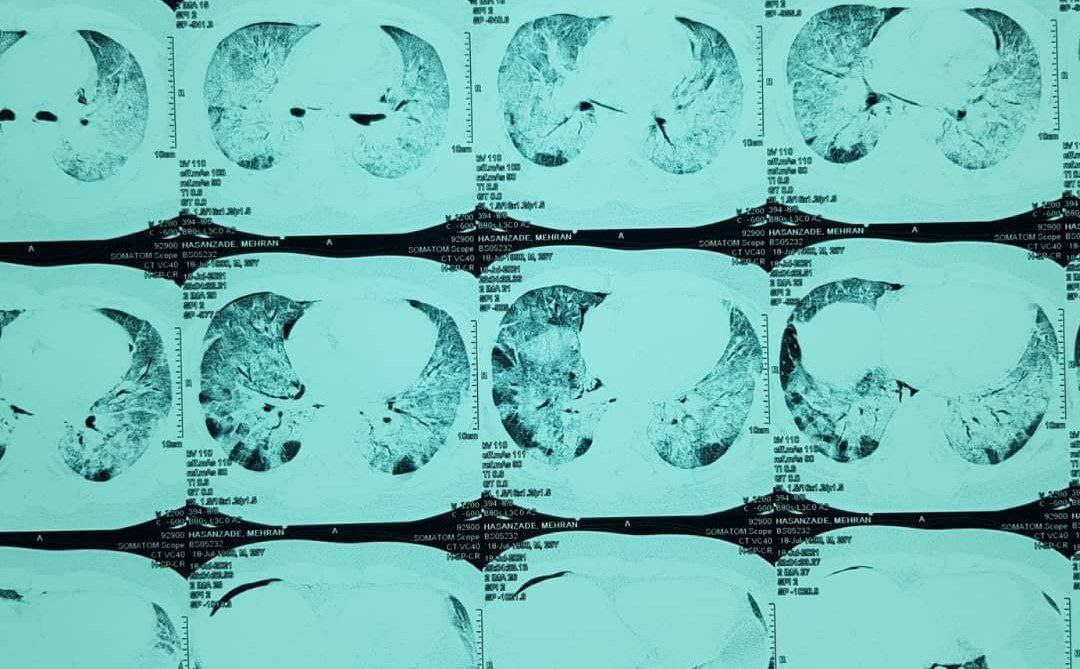

از آن‌ها اجازه خواستم تا درباره‌شان بنویسم و عکس‌ها را منتشر کنم، به این امید که مردم ببینند و بدانند که در محاصره‌ی کامل دلتا هستیم. و حتی یک‌ دورهمی کوچک هم می‌تواند چونان هجوم شوربختی بر خانه فرود آید.